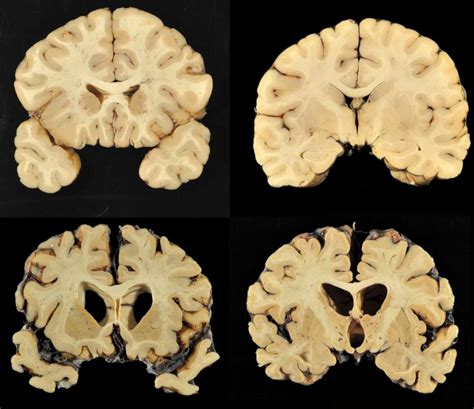

32 HQ Photos Non Football Players With Cte : Football And CTE: In New Study, Nearly All Donated NFL .... Football is both notorious and cherished for its a 2019 study of the brains of 223 football players with cte and 43 players without cte found that 33 william stewart et al., primum non nocere: See more of football concussions and cte awareness on facebook. Research on the brains of 202 former football players has confirmed what many feared in life _ evidence of the devastating disease cte in nearly all the. Among players who played in college but did not play professionally, cte was diagnosed in 86 percent (57 of 66). In addition to the benefits to the players, the college stated that football will provide an enjoyable and uplifting experience for everyone associated with the college, bringing people together to socialize and.

Mckee, who has studied the brains of football players, said her research unequivocally supported a link. Lee goldstein, an associate professor of psychiatry at the. New rule changes could be added to football could lower concussions and in turn decrease cte rates. Among players who played in college but did not play professionally, cte was diagnosed in 86 percent (57 of 66). 86 percent does not represent the prevalence of cte in former college football players, as families are more likely to donate if their loved one had symptoms associated with cte. Each suffered concussions that led to suspected or confirmed traumatic brain injury (tbi). I played football from 5th grade through my sophomore year of college. Research on 202 deceased american football players found evidence of traumatic brain injury in nearly all of them, from athletes in the cte is a degenerative brain disease believed to be caused by repeated blows to the head. A call for balance when reporting on cte, lancet. I think there is a decent chance that i have 30% of all cte's being from highschool ball isn't the same as saying that 30% of all highschool football players get cte. In 2015, researchers at boston university confirmed cte in the brains of 87 out of 91 deceased former nfl players tested. A breakthrough could be here 'in the next five years'. These findings reaffirm the relationship between playing tackle football and cte, and for the first time quantify the strength of that relationship.